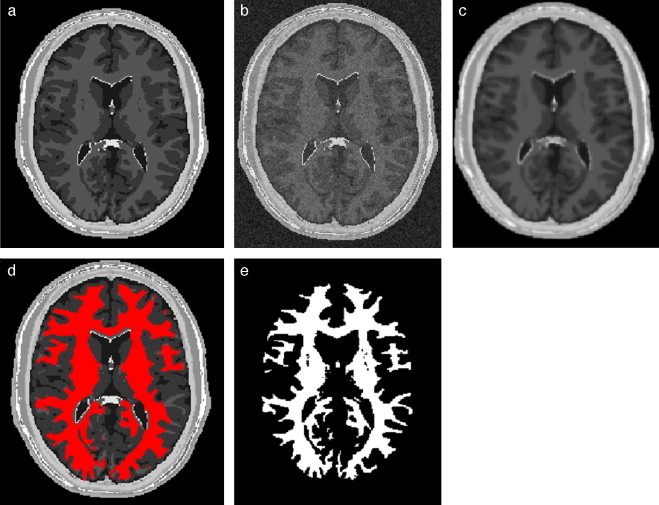

4.1. Caso 1: segmentación Region Growing - BrainWeb

Con el interés de segmentar la zona de la materia blanca, se utilizó el algoritmo de Region Growing en el phantom discreto completo original. La zona segmentada fue comparada con la zona de la materia blanca proporcionada por BrainWeb . Para este fin, se empleó el análisis de texturas con el cálculo de descriptores estadísticos en ambos volúmenes y los respectivos porcentajes de error entre ambos. En la figura 24 se presenta los resultados obtenidos al segmentar la zona de la materia blanca en el volumen phantom con dimensiones de 181 × 217 × 181 (X × Y × Z ), con voxels isotrópicos de 1,0 mm3 , por visualización se presenta el corte axial 98. En la figura 24 .a se presenta la imagen phantom original, mostrando el corte número 98 del phantom . En la figura 24 .b se presenta la zona segmentada empleando el algoritmo Region Growing con seis seed points (semillas) elegidos de manera arbitraria sobre el área de la materia blanca, en forma de esferas volumétricas de 2 mm de radio, con el centro en las coordenadas X,Y,Z : Seed1= (66,59,98), Seed2 =(67,101,98), Seed3 =(60,158,98), Seed4 =(112,55,98), Seed5 =(113,103,98) y Seed6= (127,149,58). En la figura 24 .c se presenta la zona de la materia blanca proporcionada por BrainWeb.

Materia blanca segmentada en volumen phantom. (a) Corte axial número 98 de la ...

Figura 24.

Materia blanca segmentada en volumen phantom . (a) Corte axial número 98 de la imagen de phantom original. (b) Materia blanca segmentada con metodología propuesta empleando algoritmo Region Growing. (c) Zona de la materia blanca segmentada por BrainWeb .

En la tabla 1 se presentan los valores estadísticos y los respectivos porcentajes de error, donde se puede observar que el porcentaje de error de las zonas segmentadas por Region Growing y la zona de la materia blanca proporcionada por BrainWeb no supera el 0,2487% para el caso del número global de pixels y el 0,2909% para los descriptores estadísticos.

Tabla 1. Validación del volumen de la zona de la materia blanca empleando Region Growing utilizando análisis de texturas estadísticos

Nro. pixels Media Desviación estándar Asimetría Homogeneidad Entropía

Region Growing 682.820 0,0947 0,2928 2,7687 8,6655 0,4519

Phantom BrainWeb 674.777 0,0949 0,2931 2,7641 8,6404 0,4527

%error RegionGrowing-phantom 0,2487 0,2407 0,1078 0,1644 0,2909 0,1643

4.2. Caso 2: segmentación Watershed - BrainWeb

Al igual que el caso anterior, el esquema de segmentación Watershed fue validado empleando el phantom de IRM del cerebro. En la figura 25 se presentan los resultados obtenidos al segmentar la zona de la materia blanca en el volumen phantom con dimensiones de 181 × 217 × 181 (X × Y × Z ), con voxels isotrópicos de 1,0 mm3 . En la figura 25 .a se presenta el corte número 98 de la imagen original. En la figura 25 .b se presenta la segmentación obtenida empleando el algoritmo de Watershed . En la figura 25 .c se presenta la zona de la materia blanca proporcionada por BrainWeb.

Materia blanca segmentada en volumen phantom de IRM del cerebro. (a) Corte axial ...

Figura 25.

Materia blanca segmentada en volumen phantom de IRM del cerebro. (a) Corte axial 98 de imagen de phantom original. (b) Materia blanca segmentada con metodología propuesta empleando algoritmo Watershed. (c) Zona de la materia blanca segmentada por BrainWeb .

Para validar los resultados, se empleó el análisis de texturas, calculando los descriptores estadísticos en los volúmenes obtenidos. En la tabla 2 se presentan los valores estadísticos y los respectivos porcentajes de error para ambos volúmenes. Obsérvese que el porcentaje de error del número global de pixels no supera el 1,2418%, y para los descriptores estadísticos no supera el 1,5201%.

Tabla 2. Validación del volumen de materia blanca obtenido con Watershed

Watershed 683.262 0,0961 0,2947 2,7406 8,5110 0,4565

%error Watershed-phantom 1,2418 1,2418 0,5573 0,8576 1,5201 0,8479

En la figura 26 son presentados las vistas tridimensional del volumen de la zona de la materia blanca proporcionado por BrainWeb, el volumen obtenido con Region Growing y volumen obtenido con Watershed.

Vista volumétrica de la zona de la materia blanca. (a) Volumen original de la ...

Figura 26.

Vista volumétrica de la zona de la materia blanca. (a) Volumen original de la materia blanca proporcionado por BrainWeb. (b) Vista 3D del volumen obtenido con Region Growing en la figura 26 .d. (c) Vista 3D del volumen obtenido con Watershed en la figura 27 .b.